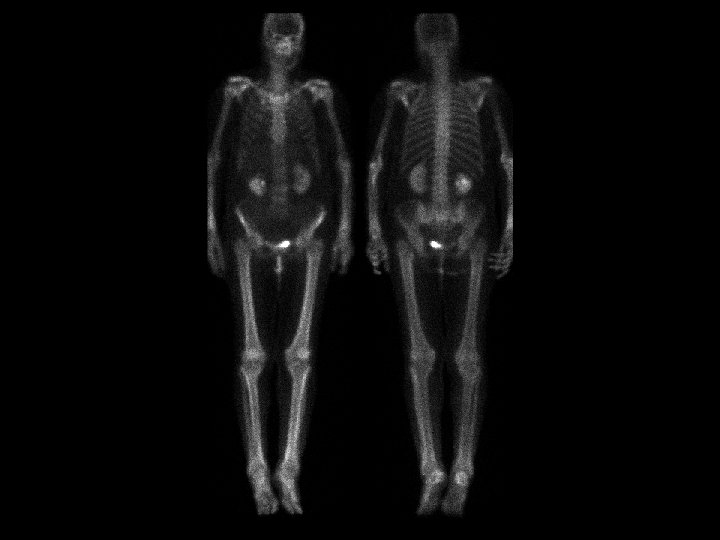

Engelmann’s disease • Findings: – Increased diaphyseal activity and expansion of the lower extremities – Radiographs show marked of the diaphyseal corticies affecting both periosteal and endosteal surfaces – Progressive diaphyseal dysplasia; autosomal dominant, variable expression • ddx: – Osteopetrosis – Melorhostosis – Hyperphosphatasia – Fibrous dysplasia